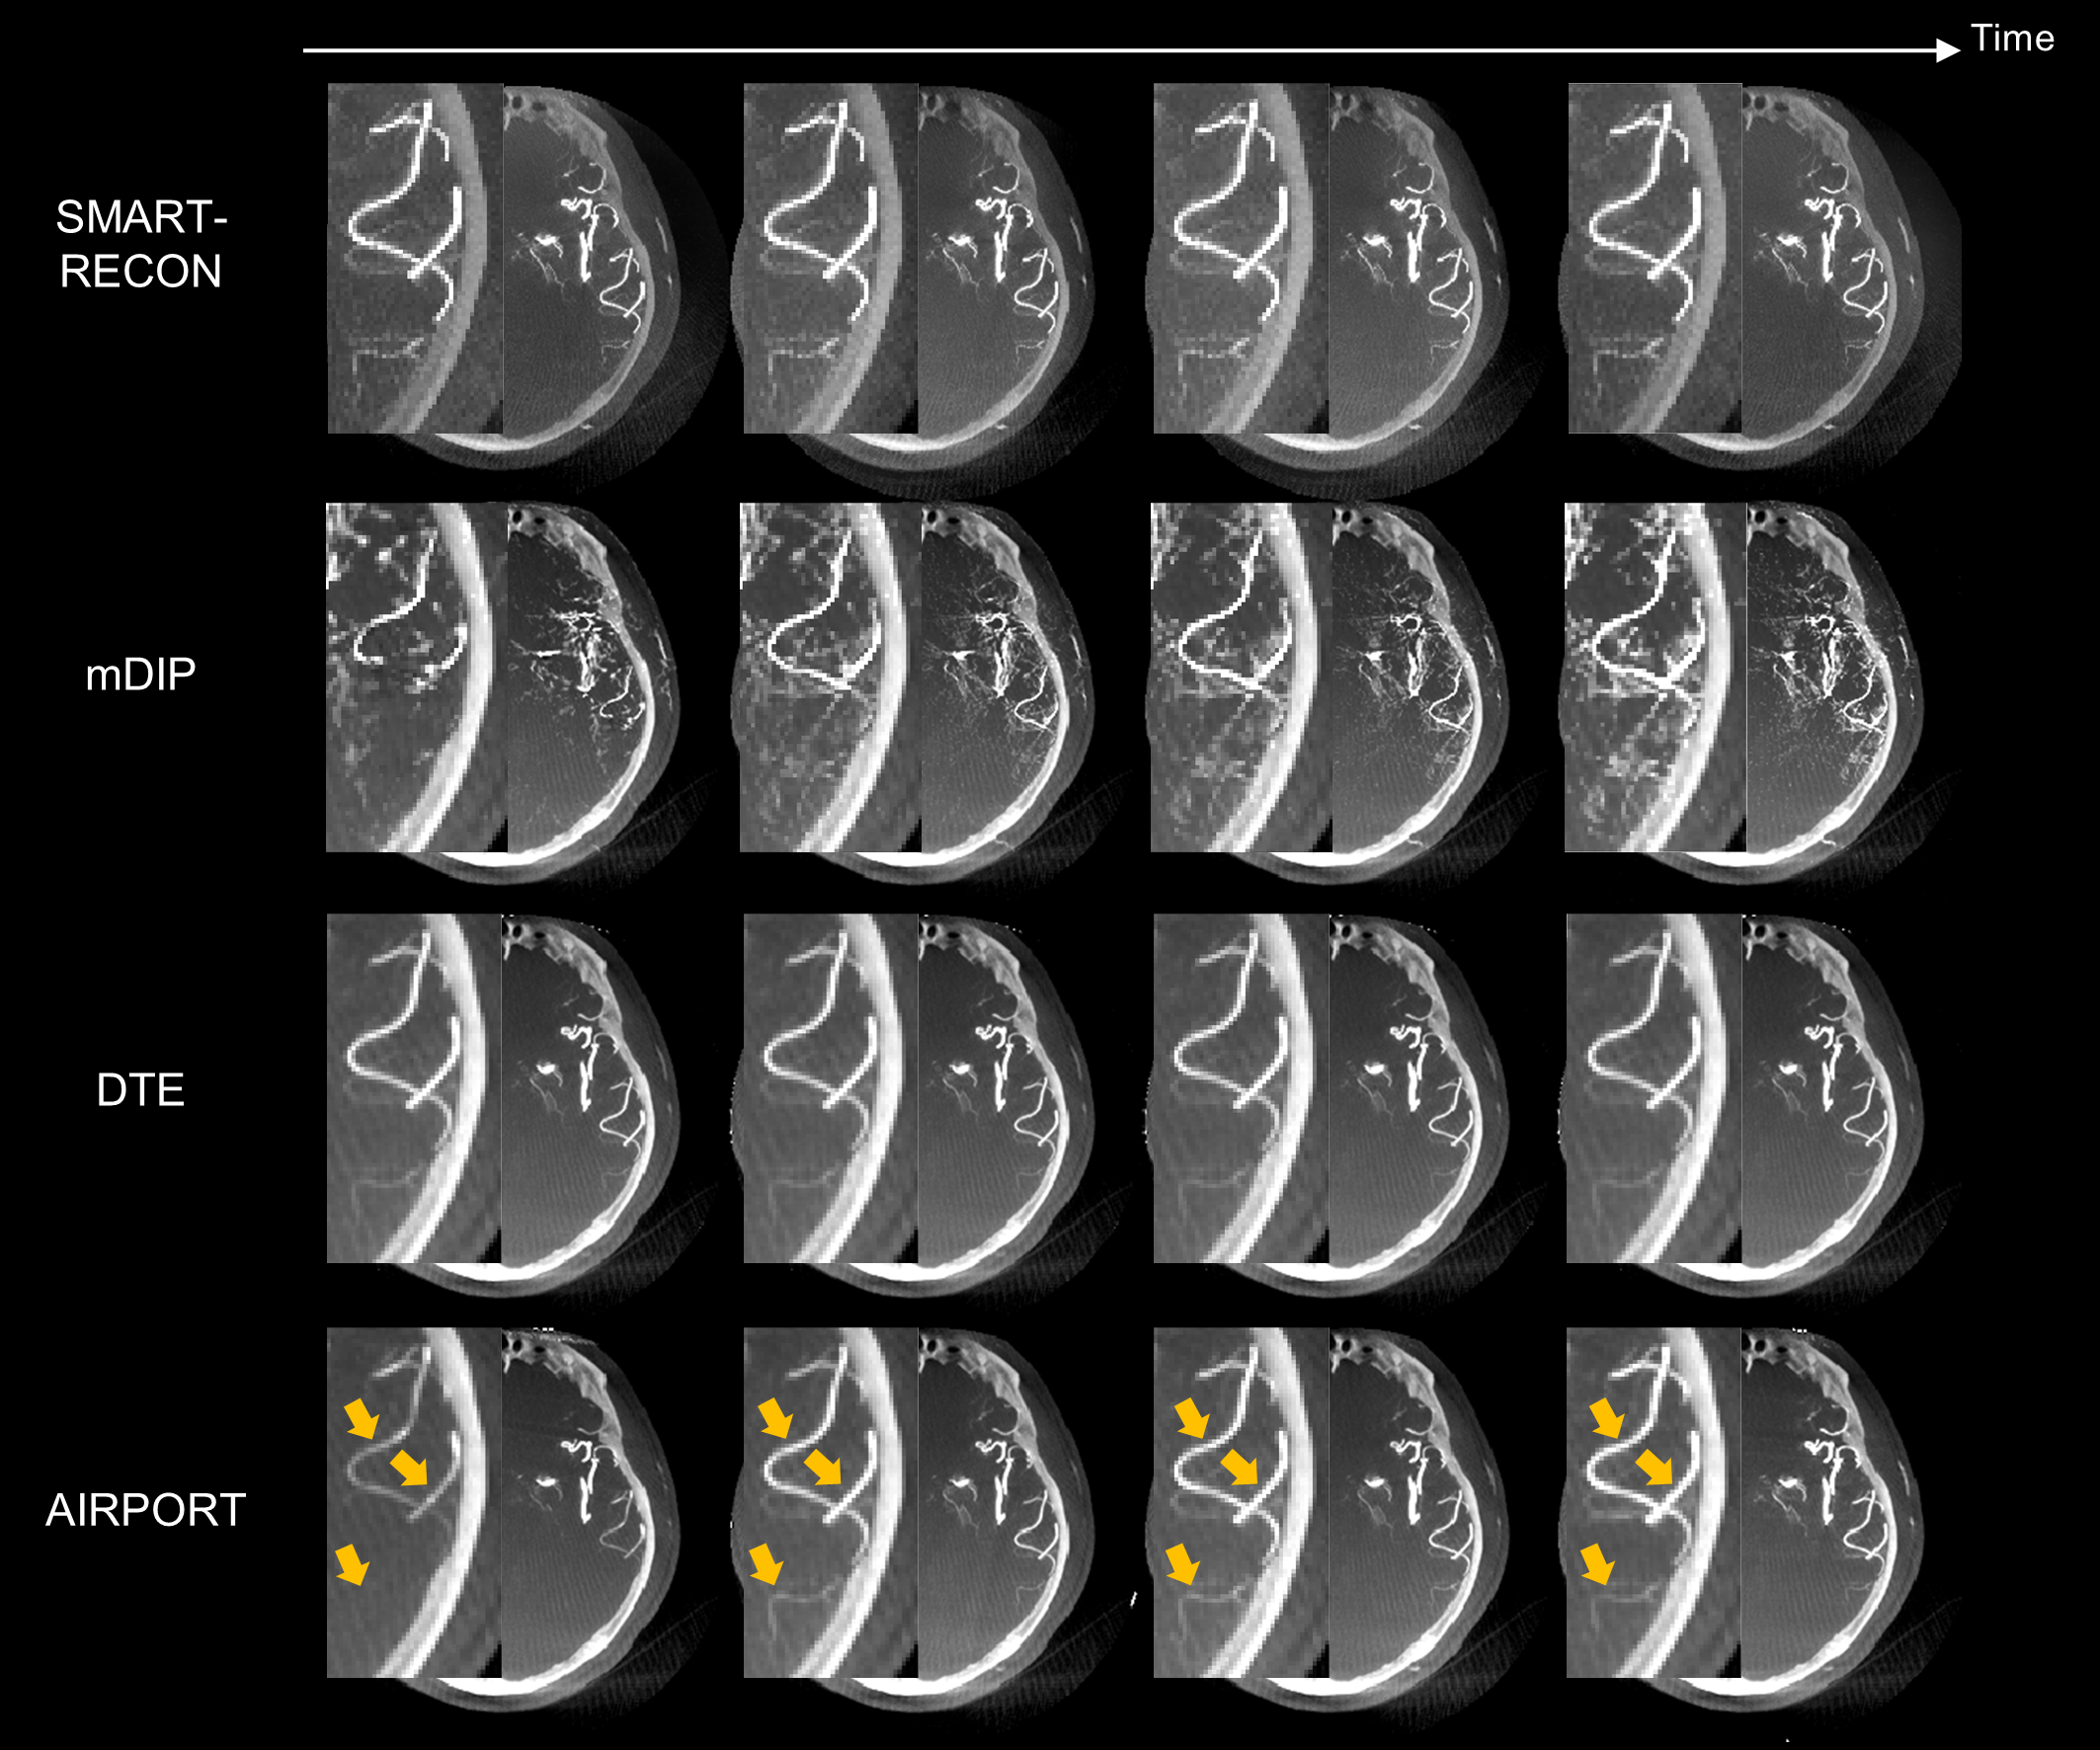

图3. 人体实验数据结果。如黄色箭头所示,提出的AIRPORT方法能够正确地重建由造影剂注射导致的动脉强度值的变化。